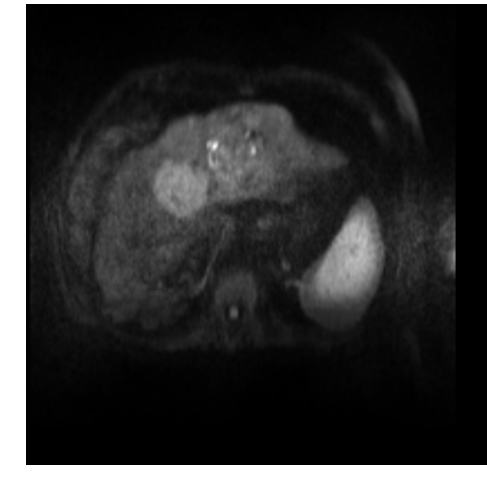

In clinical routine, manual or semi-manual segmentation techniques are applied to interprete CT and MRI images that have been acquired in the diagnosis of the liver. These techniques, however, are subjective, operator-dependent and very time-consuming. In order to improve the productivity of radiologists, computer-aided methods have been developed in the past. However, an automated robust segmentation of combined liver and lesion remains still an open problem because of challenges as a low-contrast between liver and lesion, different types of contrast levels (hyper-/hypo-intense tumors), abnormalities in tissues (such as after surgical resection of metastasis), size and varying number of lesions. As shown in figure 1 the heterogeneity in liver and lesion contrast is very large among subjects. Different acquisition protocols, differing contrast-agents, varying levels of contrast enhancements and dissimilar scanner resolutions lead to unpredictable intensity differences between liver and lesion tissue. This complexity of contrast differences make it difficult for intensity-based methods to generalize to unseen test cases from different clinical sites. In addition, the varying shape of lesions due to irregular tumor growth and response to treatment (i.e surgical resection) reduce efficiency of computational methods that make use of prior knowledge on lesion shape.

Figure 1: Liver and liver lesions slices in CT and diffusion weighted DW-MRI as well as the corresponding histogram for liver and lesions pixels in the respective modality. The shape, size and level of contrast vary for different lesions. As the histograms indicate, there is a significant overlap between liver and lesion intensities, leading to a low overall contrast.